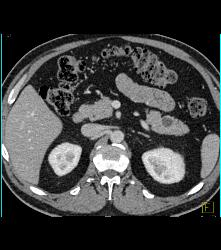

Diagnosis

Intraductal Papillary Mucinous Neoplasm (IPMN)